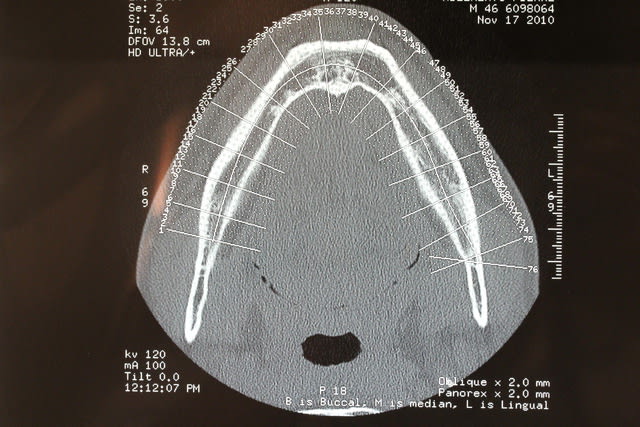

Voici le dentascan de la mandibule que je viens d ostéotenser ce jour. Deuxième séance ds 45 j et puis 45 plus tard implants en enfouis probablement

Zones molaires creuses et zones des PM denses car deux tori mandibulaires sont présent

Dès que les implants y seront vous le saurez mais vu la forme assez bizarre de la mandibule en zone molaire il y aura d abord un modèle Materialise avant la chirurgie, histoire de voir si les plaques sont indispensables ou si les disks pourront passer ds ce relief assez "courbe"

Pp ;-)